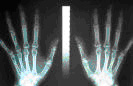

■ 骨塩定量検査(DIP法)について

レントゲン検査は骨病変の診断に最も有効で、骨の写真から「骨塩量」を測定することもできます。「タカダ医院」では、DIP法という方法で骨塩定量を行っています。この方法は階段状のアルミニウム板と第2中手骨を同時にレントゲンで撮影してアルミニウムと中手骨(骨幅・骨皮質幅・骨髄幅)との陰影濃度を比較し骨塩量を測定する方法で、日本で開発されました。骨粗しょう症の方は定期的な測定とその結果に基づいた治療が大切です。

「タカダ医院」では、あのノーベル賞で有名になった田中耕一さんが勤務する京都の「島津製作所」社製のレントゲン撮影装置(

)を導入しています。